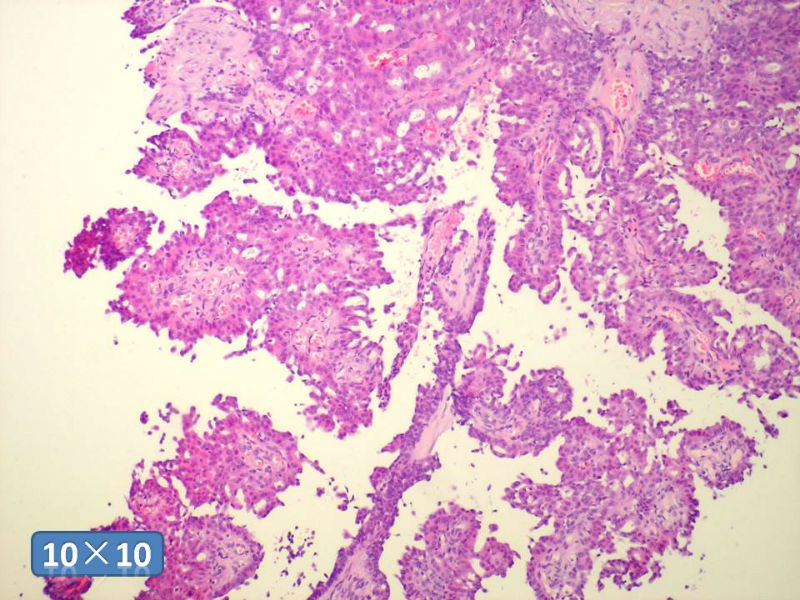

只能说是乳头状瘤

是不是导管内

乳头状瘤 and 导管内乳头状瘤 are the same; Benign lesion.

After you work up and you still cannot be sure it is benign , atypical or maignant lesion, you can call 乳头状lesion.

If this is excisonal case, you should figure out the nature of the papillary lesion.

我的意思就是提醒大家 在不是很确定的情况下 尽量少给自己套枷锁